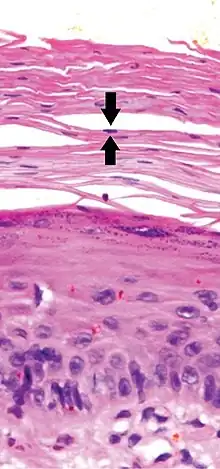

a) Focal parakeratosis b,c) prominent parakeratosis -